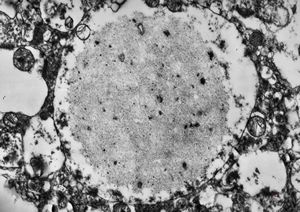

M,10y. | herpetic encephalitis